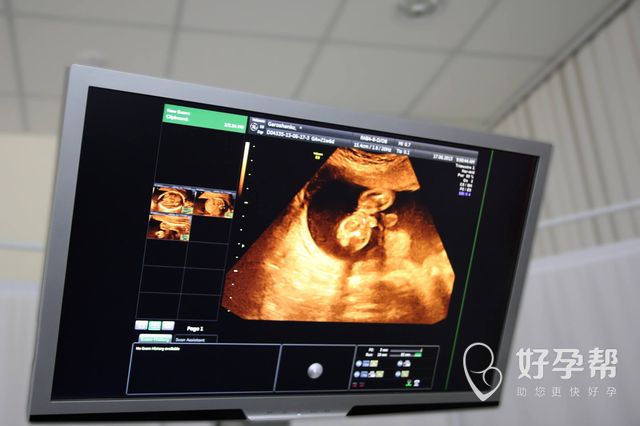

先进设备

选择沈阳试管医院一定要考察一下设备先进性,精确的设备能够给每一个医生提供最精确的数据,从而把这些数据作为诊疗标准,然而很多情况下,可能大多数患者认为只要医生技术经验设备不落伍就好,但事实并非如此试管婴儿,技术对各项要求都非常高,如果没有先进设备做保障,医生很难作出判断,也会导致大多数不孕不育患者在这方面多花冤枉钱。